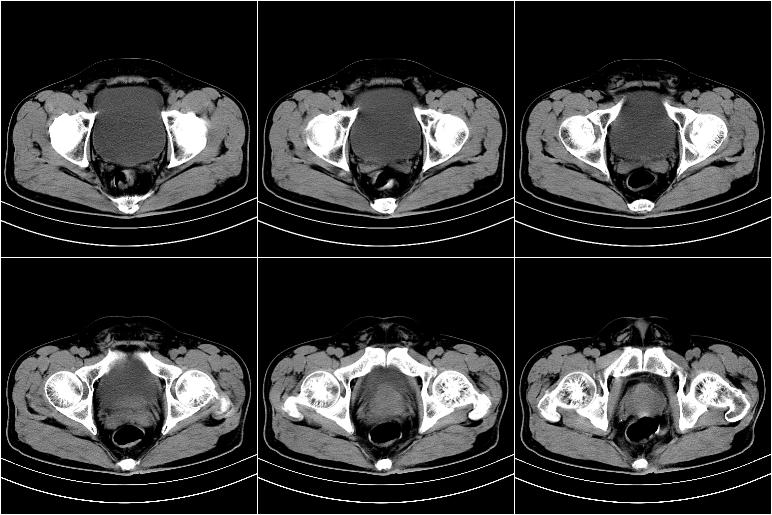

标题: CT21569:M,54Y,右侧中腹部疼痛,IVP示右侧输尿管中下段充盈缺 [打印本页]

标题: CT21569:M,54Y,右侧中腹部疼痛,IVP示右侧输尿管中下段充盈缺

ct21569和ct21569b(增强)结果:阑尾腺癌,侵犯回盲部及输尿管中段。手术切除部分升结肠、回肠及受侵4cm之输尿管,做回-横结吻合,输尿管支架置放术并吻合,术后病理腺癌,阑尾来源可能性大。